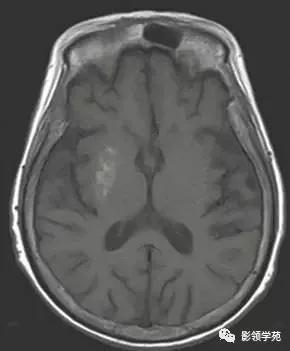

图 3 左图为四叠体池的脂肪瘤;右图为右侧颞叶的皮质层状坏死(皮质层状坏死可以发生在皮层也可以发生在深部灰质)